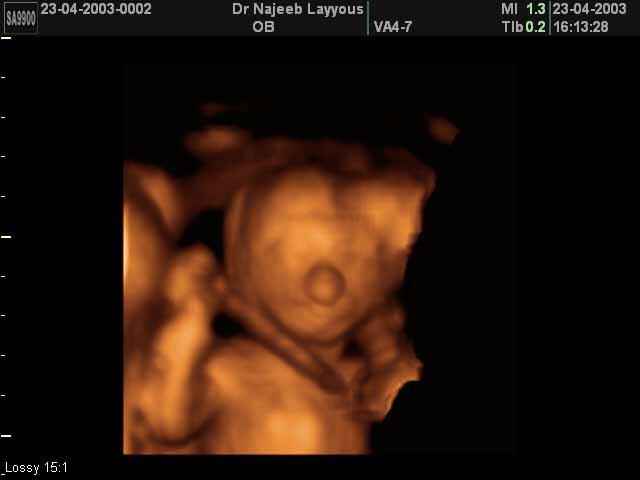

- Fetal Behavior Ultrasound Photos